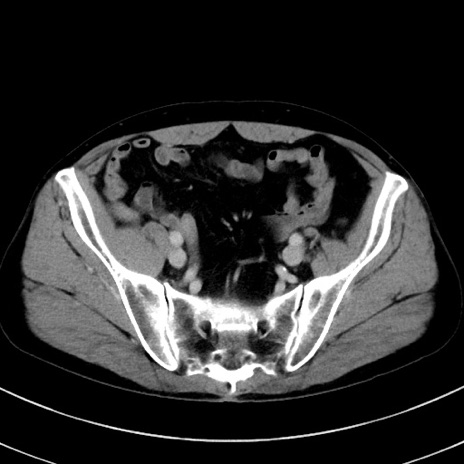

【腹部TIPS】症例44 CT(横断像)

【症例】50歳代男性

肺癌術後フォローのCT

どんな血管のanomalyが存在しますか?